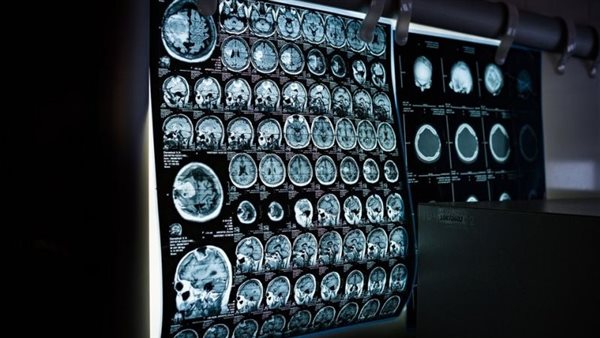

وفي الدراسة، مسح الباحثون أدمغة المشاركين باستخدام تقنية التصوير بالرنين المغناطيسي الجديدة التي تحلل حركة جزيئات الماء في الأنسجة، يمكن لهذه الطريقة أن توفر معلومات مفصلة عن البنية المجهرية للدماغ، ويمكنها اكتشاف حتى التغيرات الصغيرة جدًا في الدماغ.

وشملت الدراسة فحص 89 مريضًا يعانون من فيروس كورونا لفترة طويلة، و38 مريضًا تعافوا تمامًا من عدوى فيروس كورونا، و46 شخصًا يتمتعون بصحة جيدة ليس لديهم تاريخ للإصابة بفيروس كورونا.

وأظهرت النتائج أنهم وجدوا تغييرات طفيفة في مناطق الدماغ المختلفة التي تختلف بين الأشخاص الذين يعانون من فيروس كورونا لفترة طويلة وأولئك الذين تعافوا بشكل كامل.

ووجدوا على وجه التحديد ارتباطًا بين هذه التغيرات في البنية المجهرية وشبكات الدماغ الخاصة بأعراض ضباب الدماغ والتعب وحاسة الشم.